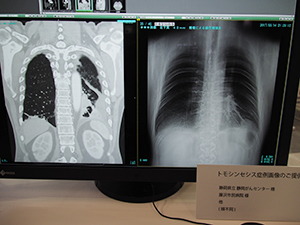

●「BENEO-Fx」のトモシンセシス撮影の臨床例を画像で紹介

一般撮影コーナーでは,トモシンセシス機能やエネルギーサブトラクション撮影機能などを搭載したデジタルX線画像診断システム「FUJIFILM DR BENEO-Fx」,ロングサイズパネル「CALNEO GL」と電動式立臥位撮影台「FM-PL1」を組み合わせた長尺撮影システムなどを展示した。

BENEO-Fxのトモシンセシス機能では,振り角は30°(15°×2),撮影時間は8秒で40枚の撮影を行う。再構成によって断層画像を生成してボリュームで観察できる。通常の一般撮影に連続して撮影でき,臥位だけでなく立位での撮影も可能で,低被ばくで患者の負担も少なく新たな診断情報が得られることが期待される。BENEO-Fxのコーナーでは,トモシンセシスの症例画像として“仙骨不顕性骨折(骨粗鬆症による脆弱性骨折)”“腰椎骨折”“播種による癌性胸膜炎”などの画像を提示し胸腹部領域でのトモシンセシスの有用性を紹介した。

播種による癌性胸膜炎の症例では,心臓裏の腫瘤が明瞭に描出されている。CTでは臥位で撮影するため胸水が貯留している場合に腫瘤部分にかぶり辺縁が不明瞭になる場合があるが,BENEO-Fxのトモシンセシス撮影では,立位撮影によって胸水がかぶることなく明瞭に描出でき,撮影線量も低いことからフォローアップなどで有効に利用できることが期待される。

トモシンセシスの症例画像:仙骨不顕性骨折 |

トモシンセシスの症例画像:腰椎骨折 |

トモシンセシスの症例画像:播種による癌性胸膜炎 |